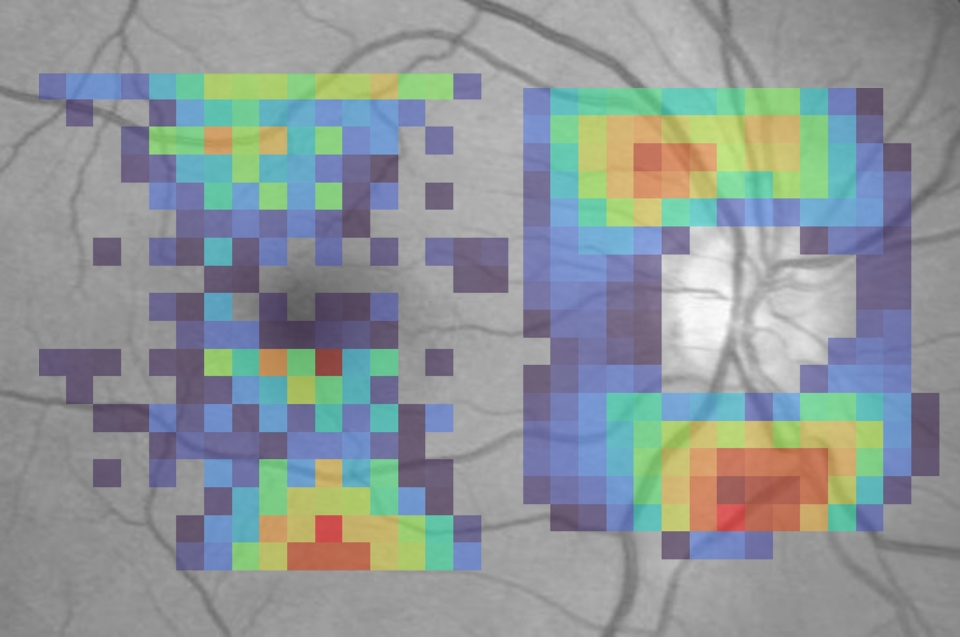

AI‑derived saliency maps overlaid on fundus photography highlight retinal regions most influential in predicting visual field loss. Warmer colors reflect higher relative contributions to visual field estimation.

Structure–to-function mapping with AI. Each square shows a point in the visual field (what they can see), while warmer colors indicate the areas of the optic nerve scan most influential for visual function at that location. Left: Saliency map based on macular OCT. Right: Saliency map based on optic nerve head OCT.

Dr. Ishikawa also employs attention analysis techniques that reveal which regions of an OCT image the AI examines to generate its predictions. "We can generate a heat map," he explains. Traditional mapping divides the visual field into six sectors. "AI gives us a high-definition version of structure-function mapping."